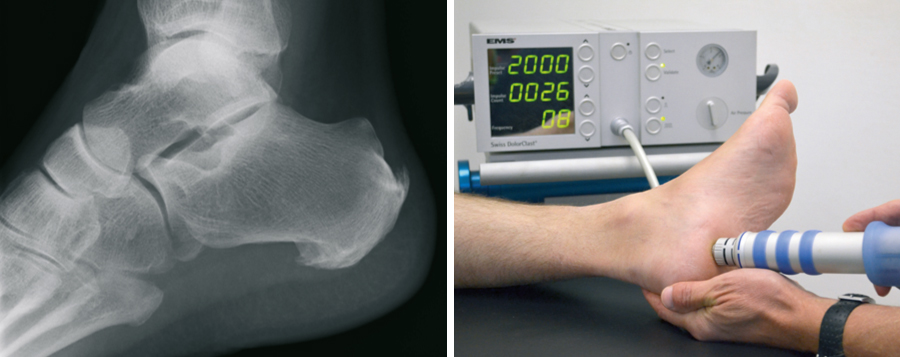

Fersensporn

Der plantare Fersensporn (unten an der Ferse) entsteht durch eine Überlastung der das Fußlängsgewölbe verspannenden Faszie. Bindegewebsschwäche, Fehlbelastung, Fehlstellung, aber auch Übergewicht können hierfür verantwortlich sein. Durch die Überlastung entsteht zwischen dem Fersenbein und der Anhaftungsstelle dieser Faszie eine zunehmende Gewebeschädigung, verbunden mit einer Verknöcherung, dem sogenannten Fersensporn. Nicht der Sporn selbst, sondern diese Gewebeschädigung verursacht die Schmerzen. Sie treten zunächst vorwiegend belastungsabhängig auf, später aber auch in Ruhe. An erster Stelle der möglichen Behandlungen steht die Versorgung mit speziellen orthopädischen Einlagen. Auch Injektionen, direkt an den Fersensporn, haben ihren Stellenwert. Sehr bewährt hat sich die risikofreie Stoßwellentherapie, die auch in unserer Praxis durchgeführt wird. Alternativ kann Röntgenbestrahlung eine Ausheilung bewirken.

Versagen alle nicht operativen Maßnahmen, besteht auch hier eine operative Behandlungsmöglichkeit. Dabei wird über einen kleinen Schnitt am inneren Fersenrand die Faszie eingekerbt, die Spannung lässt nach und die Gewebeschädigung kann ausheilen.